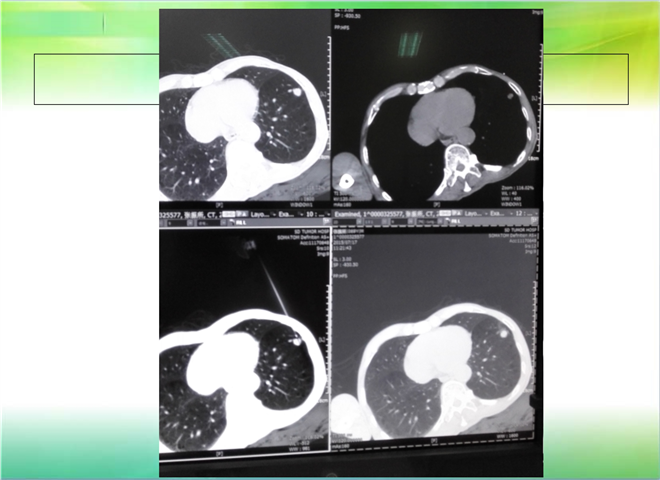

CT引导下穿刺活检术